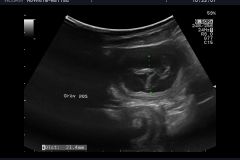

Das, was wir schon vermutet hattten, wurde uns heute, durch unseren Tierarzt bestätigt: Happy"ist trächtig . Wir werden um den 20.04.2024 Welpen in noir bekommen. Es wird für Happy ihr  letzter Wurf sein. Sie hat immer große Würfe gehabt und hat diese problemlos großgezogen. Wir hoffen und wünschen uns das es bei ihrem letzten Wurf auch so schnell, geht wie bei ihren beiden ersten Würfen. Namen mit L werden diesmal gesucht, drei Namen stehen schon fest La Luna , Le Soleil un L´Jiott.

Happy war es wohl zu heiß um im Hochsommer Welpen zu haben. Der Ultraschall hat ergeben, es gibt keine Welpen . Im Januar werden wir es wieder versuchen und bei Interesse können Sie sich gerne melden.